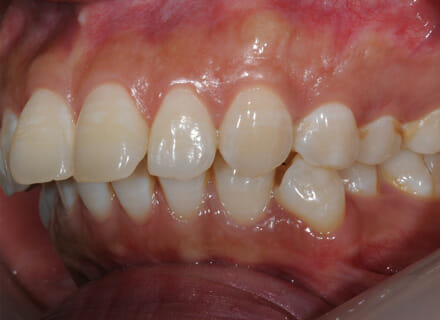

This lady came to us because she said she was goofy – her front teeth were sticking out. In the lower jaw, the teeth didn’t have enough room so 2 teeth had been pushed out of the bite altogether. We fitted a clear brace and were able to reduce the overbite by 80%. We also managed to pull the lower premolars back into the arch. This lady did not require any extractions. She was so pleased with the results especially as no healthy teeth were removed!